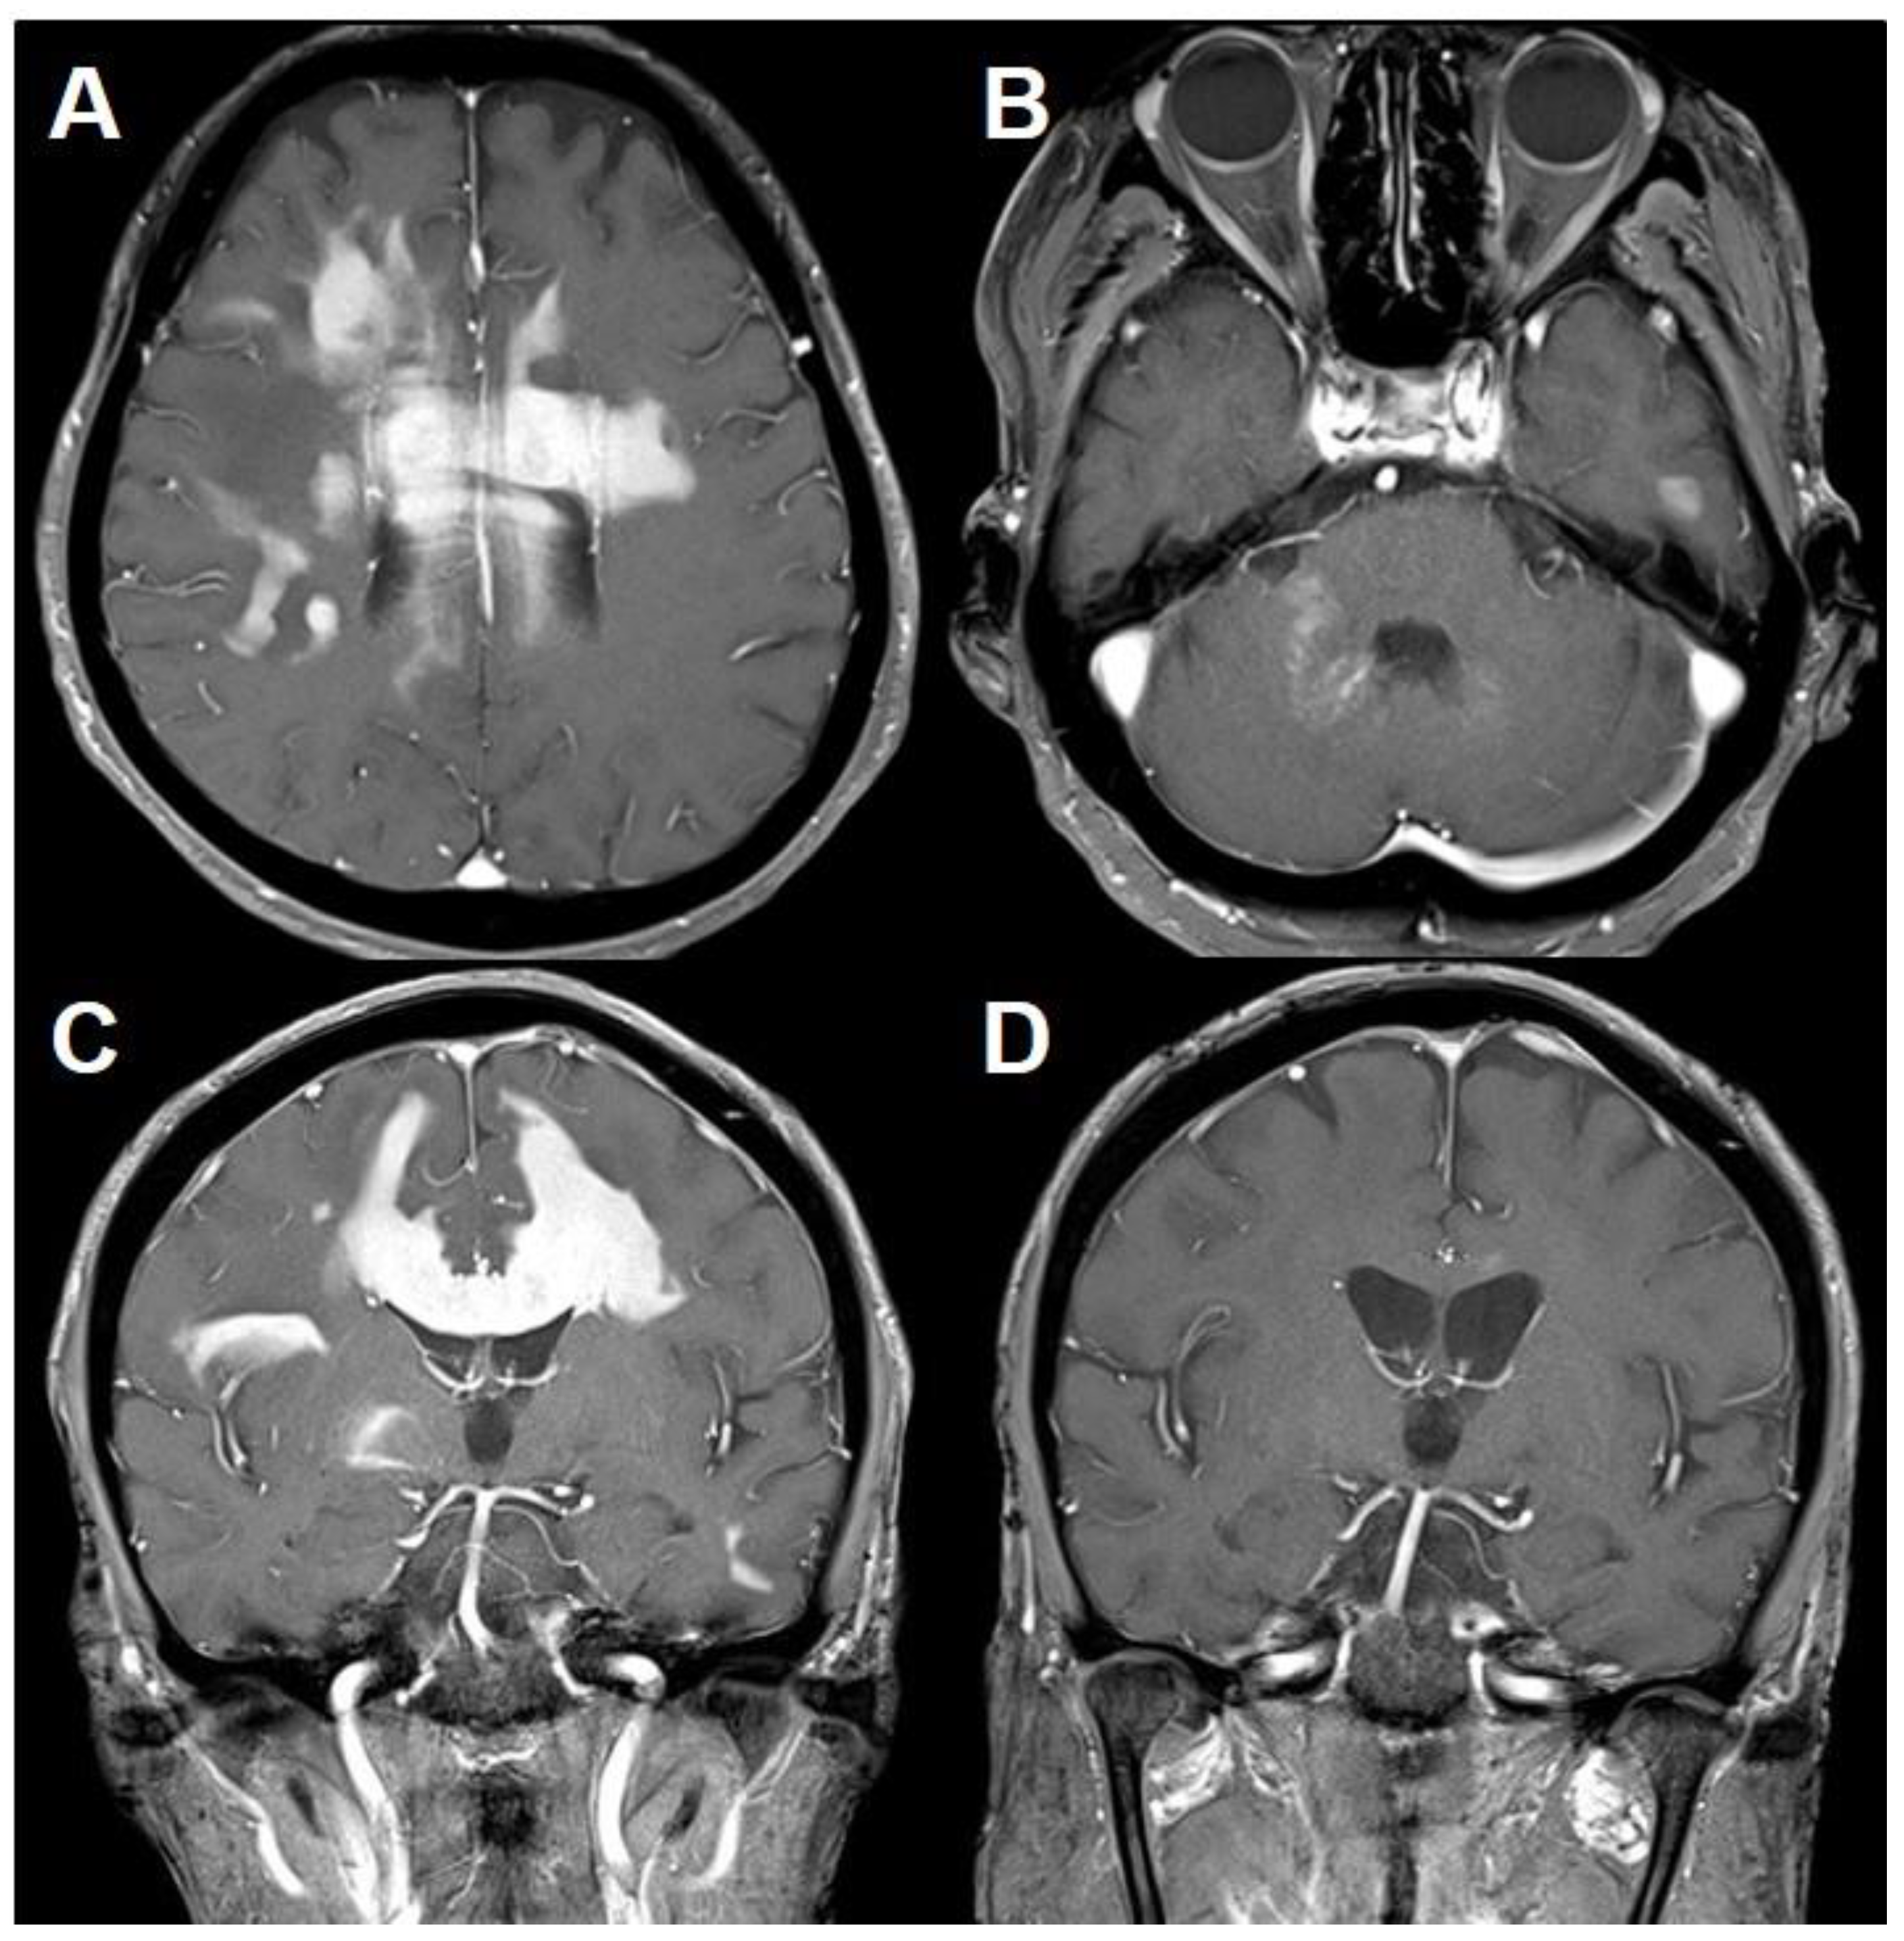

| 7 (current case) | 70/F | Facial numbness Hemiparesthesia | Homogenous enhancing lesion | Inflammatory lesion with mixed T/B-cell infiltration without demyelination | Corticosteroid | 26 | Quadriparesis Mental change | Homogenous enhancing lesions | PCNSL (B-cell) | MTX-chemotherapy | 38 mos survival |